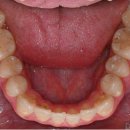

보냅니다. 기공소에서는 이 정보를 바탕으로 개인 맞춤형 크라운을 제작합니다. 제작된 크라운은 다시 명일역치과로 보내지며, 치과 전문의는 이 크라운을 손상된 치아에 부착합니다. 이렇게 해서 손상된 치아는 새로운 크라운으로 보호받게 되며, 기능 또한 복원됩니다. 명일역치과에서는 이런 크라운치료 과정을...

진료 후기를 알려드릴게요! 무삭제 쎄라필름이란? 2D치과(투디치과) 2D치과(투디치과) 무삭제 쎄라필름 보통 무삭제 쎄라필름을 하러 오시는 분은 깨진 앞니, 벌어진 치아, 누런 치아 등, 케이스가 다양해요. 무삭제 쎄라필름은 0.1mm최소 두께로 치아 손상 없이 얇은 막으로 치아를 보호하는 진료이기 때문에 삭제...